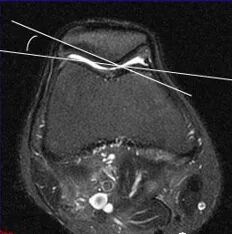

影像学检查

• X线检查:髌骨切线位ⅹ线片对诊断髌趿排列乱及股骨髁发育不良具有十分重要的诊断价值,是髌骨软化症病因诊断常用方法。

• CT检查:对诊断髌股排列错乱及股骨髁发育不良有诊断价值,可作为X线片诊断的补充手段。其优点是能显示髌骨关节面病变及髌股关节间隙狭窄更清楚,也可以显示部分髌骨软骨病变。

膝关节屈曲20度摄髌股关节轴位片,观察股骨内外侧髁前面切线与髌骨外侧关节面切线的交角,即外侧髌股角Laurin角),正常应开向外侧,而异常的开向内侧。即髌骨外翻外移。